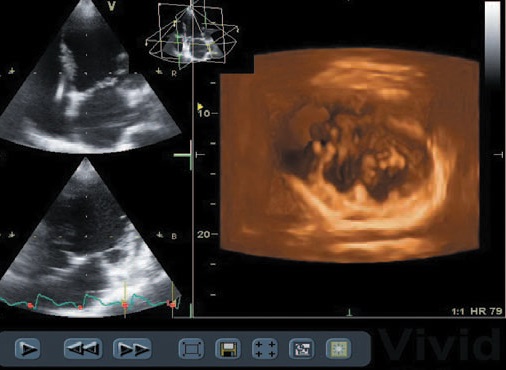

การตรวจหัวใจด้วยคลื่นเสียงสะท้อนระบบ 3 มิติ (3-D Echocardiography) เป็นวิธีการตรวจหัวใจโดยใช้คลื่นเสียงสะท้อนในระบบ 3 มิติ เพื่อการวินิจฉัยโรค รูปที่ได้จะมีความชัดและความลึกแบบ 3 มิติชัดเจนกว่าการตรวจด้วยเครื่องระบบ 2 มิติแบบเก่า